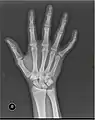

X-ray

Fracture

The neck of a metacarpal is a common location for a boxer's fracture, but all parts of the metacarpal bone (including head, body and base) are susceptible to fracture. During their lifetime, 2.5% of individuals will experience at least one metacarpal fracture. Bennett's fracture (base of the thumb) is the most common.[4] Several types of treatment exist ranging from non-operative techniques, with or without immobilization, to operative techniques using closed or open reduction and internal fixation (ORIF). Generally, most fractures showing little or no displacement can be treated successfully without surgery.[5] Intraarticular fracture-dislocations of the metacarpal head or base may require surgical fixation, as fragment displacement affecting the joint surface is rarely tolerated well.[5]

X-ray image of right hand with thumb on left.

Multiple fractures of the metacarpals (aka broken hand). (Right hand shown with thumb on left.)